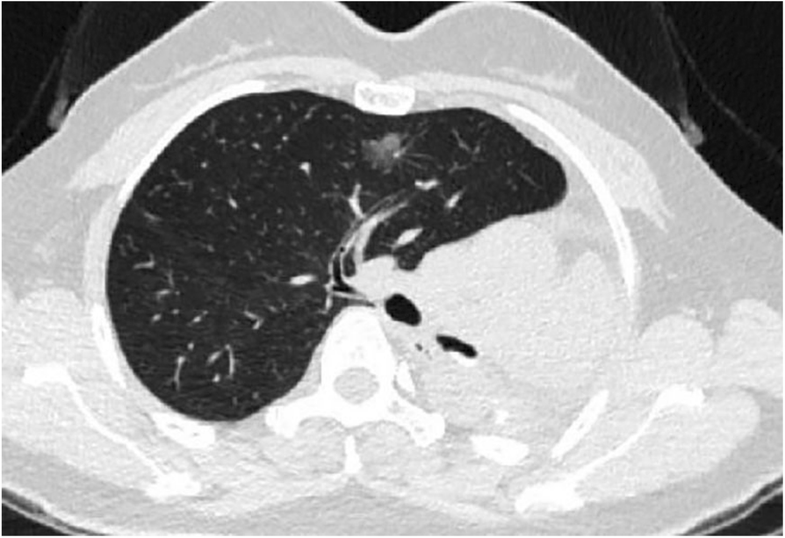

A 48-year old woman (weight 52 kg, height 152 cm, ASA II) was admitted in Sept 18th 2016 because of a ground glass opacity (GGO) which had been detected in the right lung 2 years ago. She had her left pneumonectomy through uniportal VATS owing to the left upper lobe adenocarcinoma invasive to the left main bronchus in Mar 2014. Her pre-operative diagnoses were GGO in the right upper lobe, suspect for malignancy and left postpneumonectomy (Fig. 1). No abnormal findings were detected among other tests, and some of the important figures in the arterial blood gas test were showed as follows: pH 7.44, PaCO2 37 mmHg, PaO2 84 mmHg, SaO297.7%. Her pulmonary function test showed FEV1 46.9%, FEV1/FVC 83.3%, and her predicted postoperative FEV1% would be close to 44.7%. Although other tests of evaluating cardiopulmonary reserve function and lung parenchymal function were not performed, her regular 3-floor climbing activity was not compromised. The operation was scheduled as right anterior segmentectomy through uniportal VATS under general anesthesia. Routine monitoring was applied and the first data were recorded as follows: body temperature 36.7 °C, blood pressure 123/70 mmHg, heart rate 86/min and Sp02 98% when the patient was placed in a supine position in the operation room. After the insertion of an 18-gauge intravenous cannula and the right internal jugular vein catheter, intravenous induction was carried out with an injection of midazolam 0.03 mg/kg, sufentanil 0.6 μg/kg, propofol 1 mg/kg, and rocuronium 0.8 mg/kg. Intubation preparation: the patient was scheduled to have the right anterior segmentectomy through VATS after the left pneumonectomy, which entailed us to make a good balance between ventilation and collapse on the right lung only, to make good use of ventilation in the lower and middle lobes, and to produce an effective collapse in the upper lobar. After a prudent study of the following parameters, the diameter of the narrowest part of the tracheal is 11.9 mm, the length of right upper lobe bronchus is 6.2 mm, the angle of the right main bronchus and right upper lobe bronchus is close to 90 degree, the diameter of the bronchus intermedius is 8.8 mm, and the length of bronchus intermedius is about 15 mm, a 32 Fr left-sided DLT was chosen and adapted (Fig. 2). Permission was granted by our hospital ethical committee to adapt the DLTs. The cutting edge of the tube should be smooth and clean, only in this way can we make sure that it won’t do any harm to the airways. One cut (cut just for once) would be best in adapting. Whether the cutting edge is qualified or not can be detected by our sensitive finger tips. And this technique has been proved safe from our experience in tracheal and bronchial operations. The 32Fr left-sided DLTs have been used among short women for left thoracic operations in our facility, and its external diameter is about 10.7 mm, the bronchial internal diameter is about 3.5 mm. But it’s our first time to insert the left-sided DLT to the right for the right lung surgery. As we can see from Fig. 1, the mediastinum has shifted to the left, the intubation should be gentle and carried out by an experienced anesthesiologist in case of any possible injury or even perforation to the former carina. After induction, we performed a FOB (3.0 mm diameter) guided endobronchial intubation with the bronchial cuff into the right bronchus intermedius, and the tracheal cuff’s orifice up against the upper bronchial port (Fig. 3), in this way, the ventilation of the dependent right middle and lower lobes and the collapse of the upper lobar were guaranteed (Fig. 4), thus an appropriate balance between surgical field and oxygenation was achieved, and the blood and sputum from the upper lobe bronchial port can be sucked out. An automatic infusion of propofol and sufentanil combined with manual administration of rocuronium maintained the anesthesia for the operation. And a lung protective mechanical ventilation strategy was taken, positive end-expiratory pressure (PEEP) 5 cmH2O, tidal volume (Vt) 4–6 ml/kg, frequency 15–18/min. In the meantime, end tidal CO2 and arterial blood gas analysis were recorded to adjust ventilation. The lung recruitment, air leak test and sputum suction went well throughout the operation and the surgery was completed as planned. The patient recovered well after the surgery, so she was extubated in the operation room and sent to the postanesthesia care unit (PACU) for transition, where a routine oxygen supplementation was applied. Oxygenation, ventilation, and circulation were all strictly monitored and no adverse events were recorded in the PACU. She recovered better on the next day follow-up and was discharged from the hospital 6 days later. The pathological diagnosis was invasive adenocarcinoma.

Fig. 1

CT (computed tomography) scan of the right anterior GGO (ground glass opacity) and postpneumonectomy